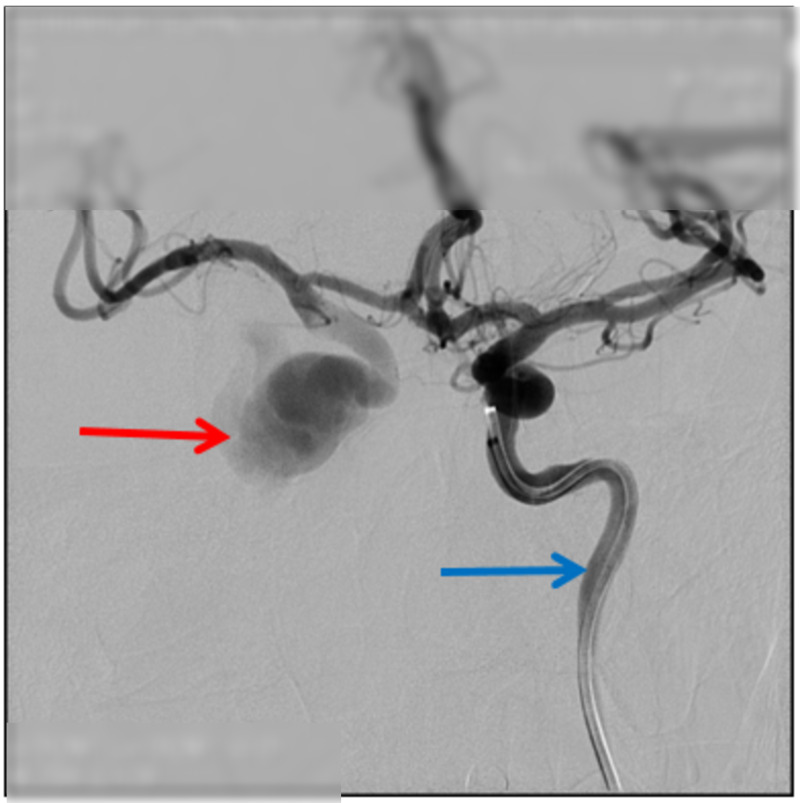

颈海绵状瘘(CCFs)是颈动脉和海绵窦之间异常的动静脉连接,由外伤引起。本病例报告提出一位47岁男性,在道路交通事故后发展为CCF。患者表现出搏动性眼球突出和眼球杂色等症状,这是CCFs的特征。通过数字减影血管造影(DSA)确认诊断,显示瘘的来源。患者采用显微手术和血管内介入治疗的新方法,包括内颈动脉结扎和经动脉线圈栓塞。治疗后症状迅速缓解,包括搏动性眼球突出和眼压。本病例强调了多学科方法的重要性,结合显微外科和先进的血管内技术,有效地治疗创伤性CCFs。该研究强调了早期诊断的价值和微创手术在改善患者预后方面的作用。

Carotid-Cavernous Fistulas (CCFs) are abnormal arteriovenous connections between the carotid artery and the cavernous sinus, resulting from trauma. This case report presents a 47-year-old male who developed a CCF following a road traffic accident. The patient exhibited symptoms such as pulsatile exophthalmos and an ocular bruit, characteristic of CCFs. Diagnosis was confirmed through Digital Subtraction Angiography (DSA), revealed the origin of the fistula. The patient was treated using a novel combined approach of microsurgery and endovascular intervention, involving ligation of the internal carotid artery and transarterial coil embolization. The treatment resulted in rapid resolution of symptoms, including the pulsatile exophthalmos and ocular bruit. This case highlights the importance of a multidisciplinary approach, blending microsurgical and advanced endovascular techniques, in effectively managing traumatic CCFs. The study underscores the value of early diagnosis and the evolving role of minimally invasive procedures in improving patient outcomes.